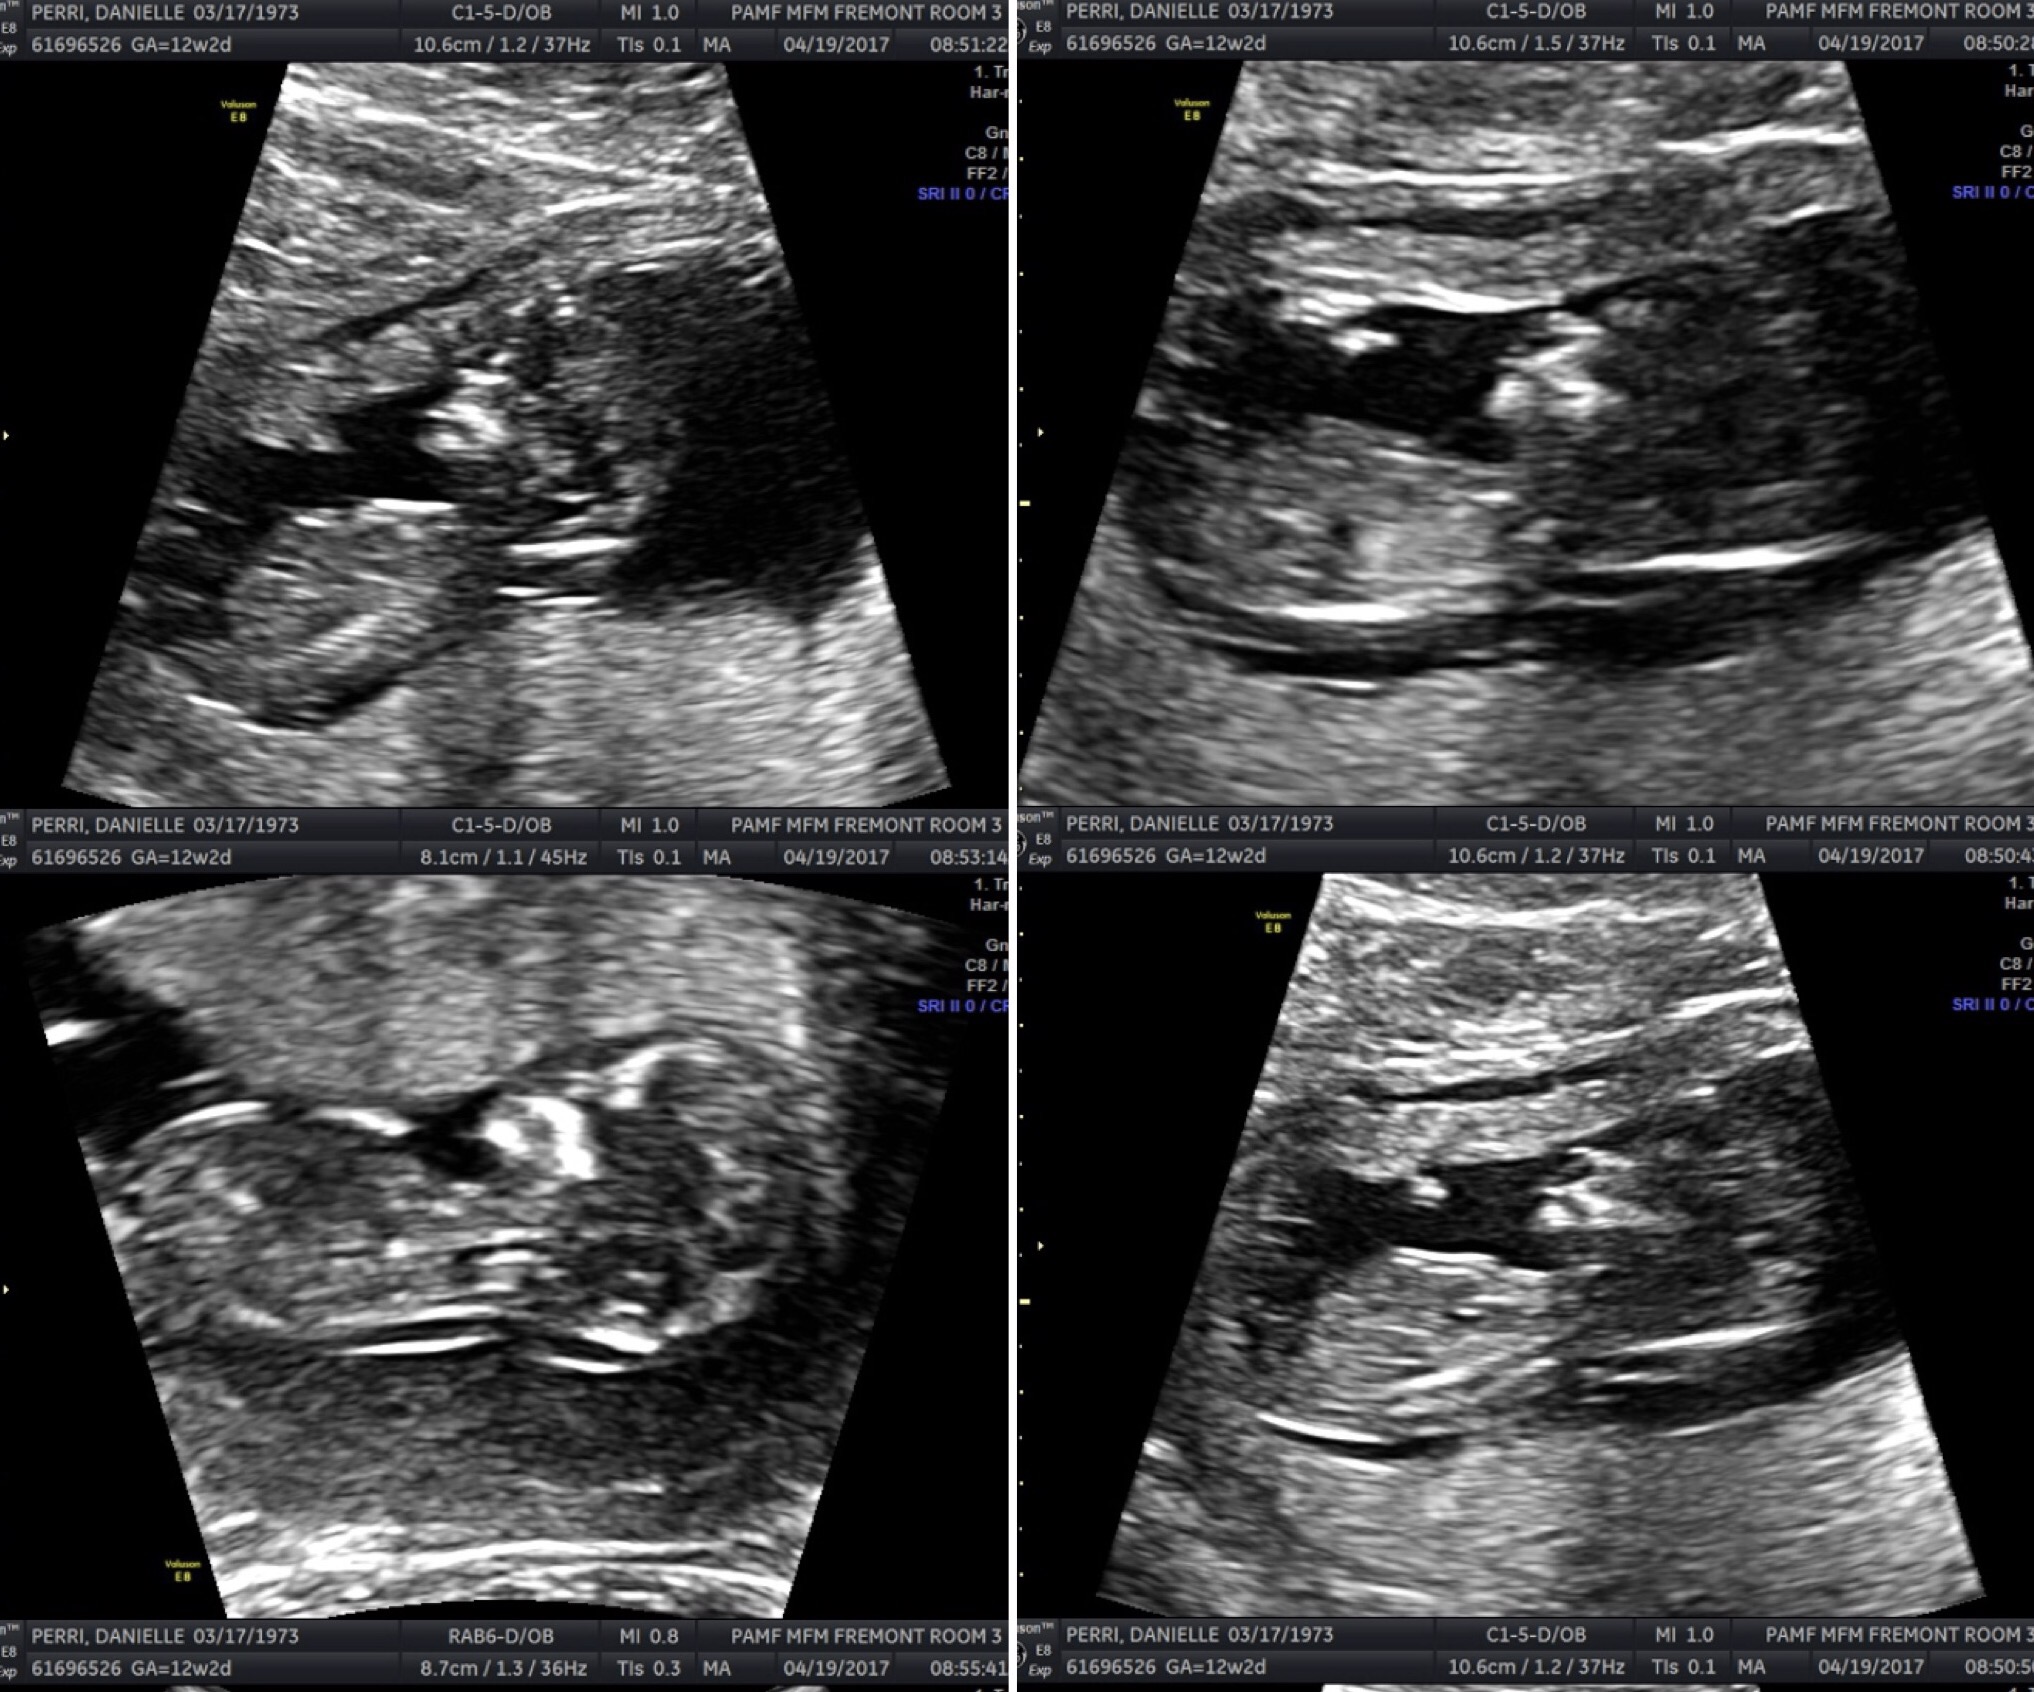

This sonogram series was taken about a month after the first, and while the baby structures are still hard for me to make out, the heartbeat looks so strong and even.